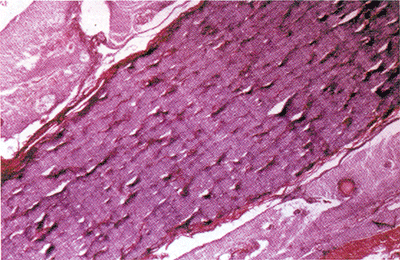

此瘤起源于覆盖硬膜或蛛网膜的内皮细胞,故亦称为内皮细胞瘤。最常见一般是在硬脑膜内,但最后它会向硬脑膜的内外蔓延。因与骨质不接触,它在眶内生长很自由,不引起眶壁的改变。 显微镜下可以看到脑膜瘤是由许多细胞草组成。细胞巢可全无或仅有很少的结缔组织纤维。肿瘤周围可以只被薄壁血管分开,沙粒体在脑膜瘤中是常见的。